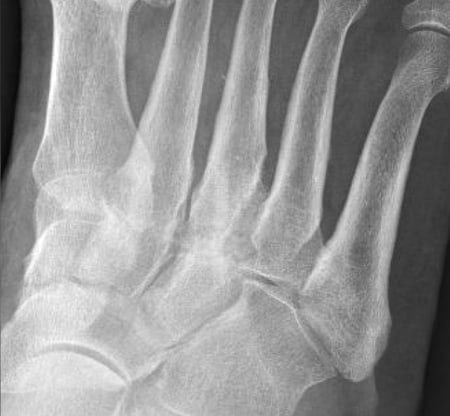

1 Jahr postoperativ

Vollständige reaktionslose Arthrodese der TMT Gelenke II und III, die Shark Screw® Transplantate kaum noch sichtbar, es ist daraus patienteneigener Knochen entstanden.